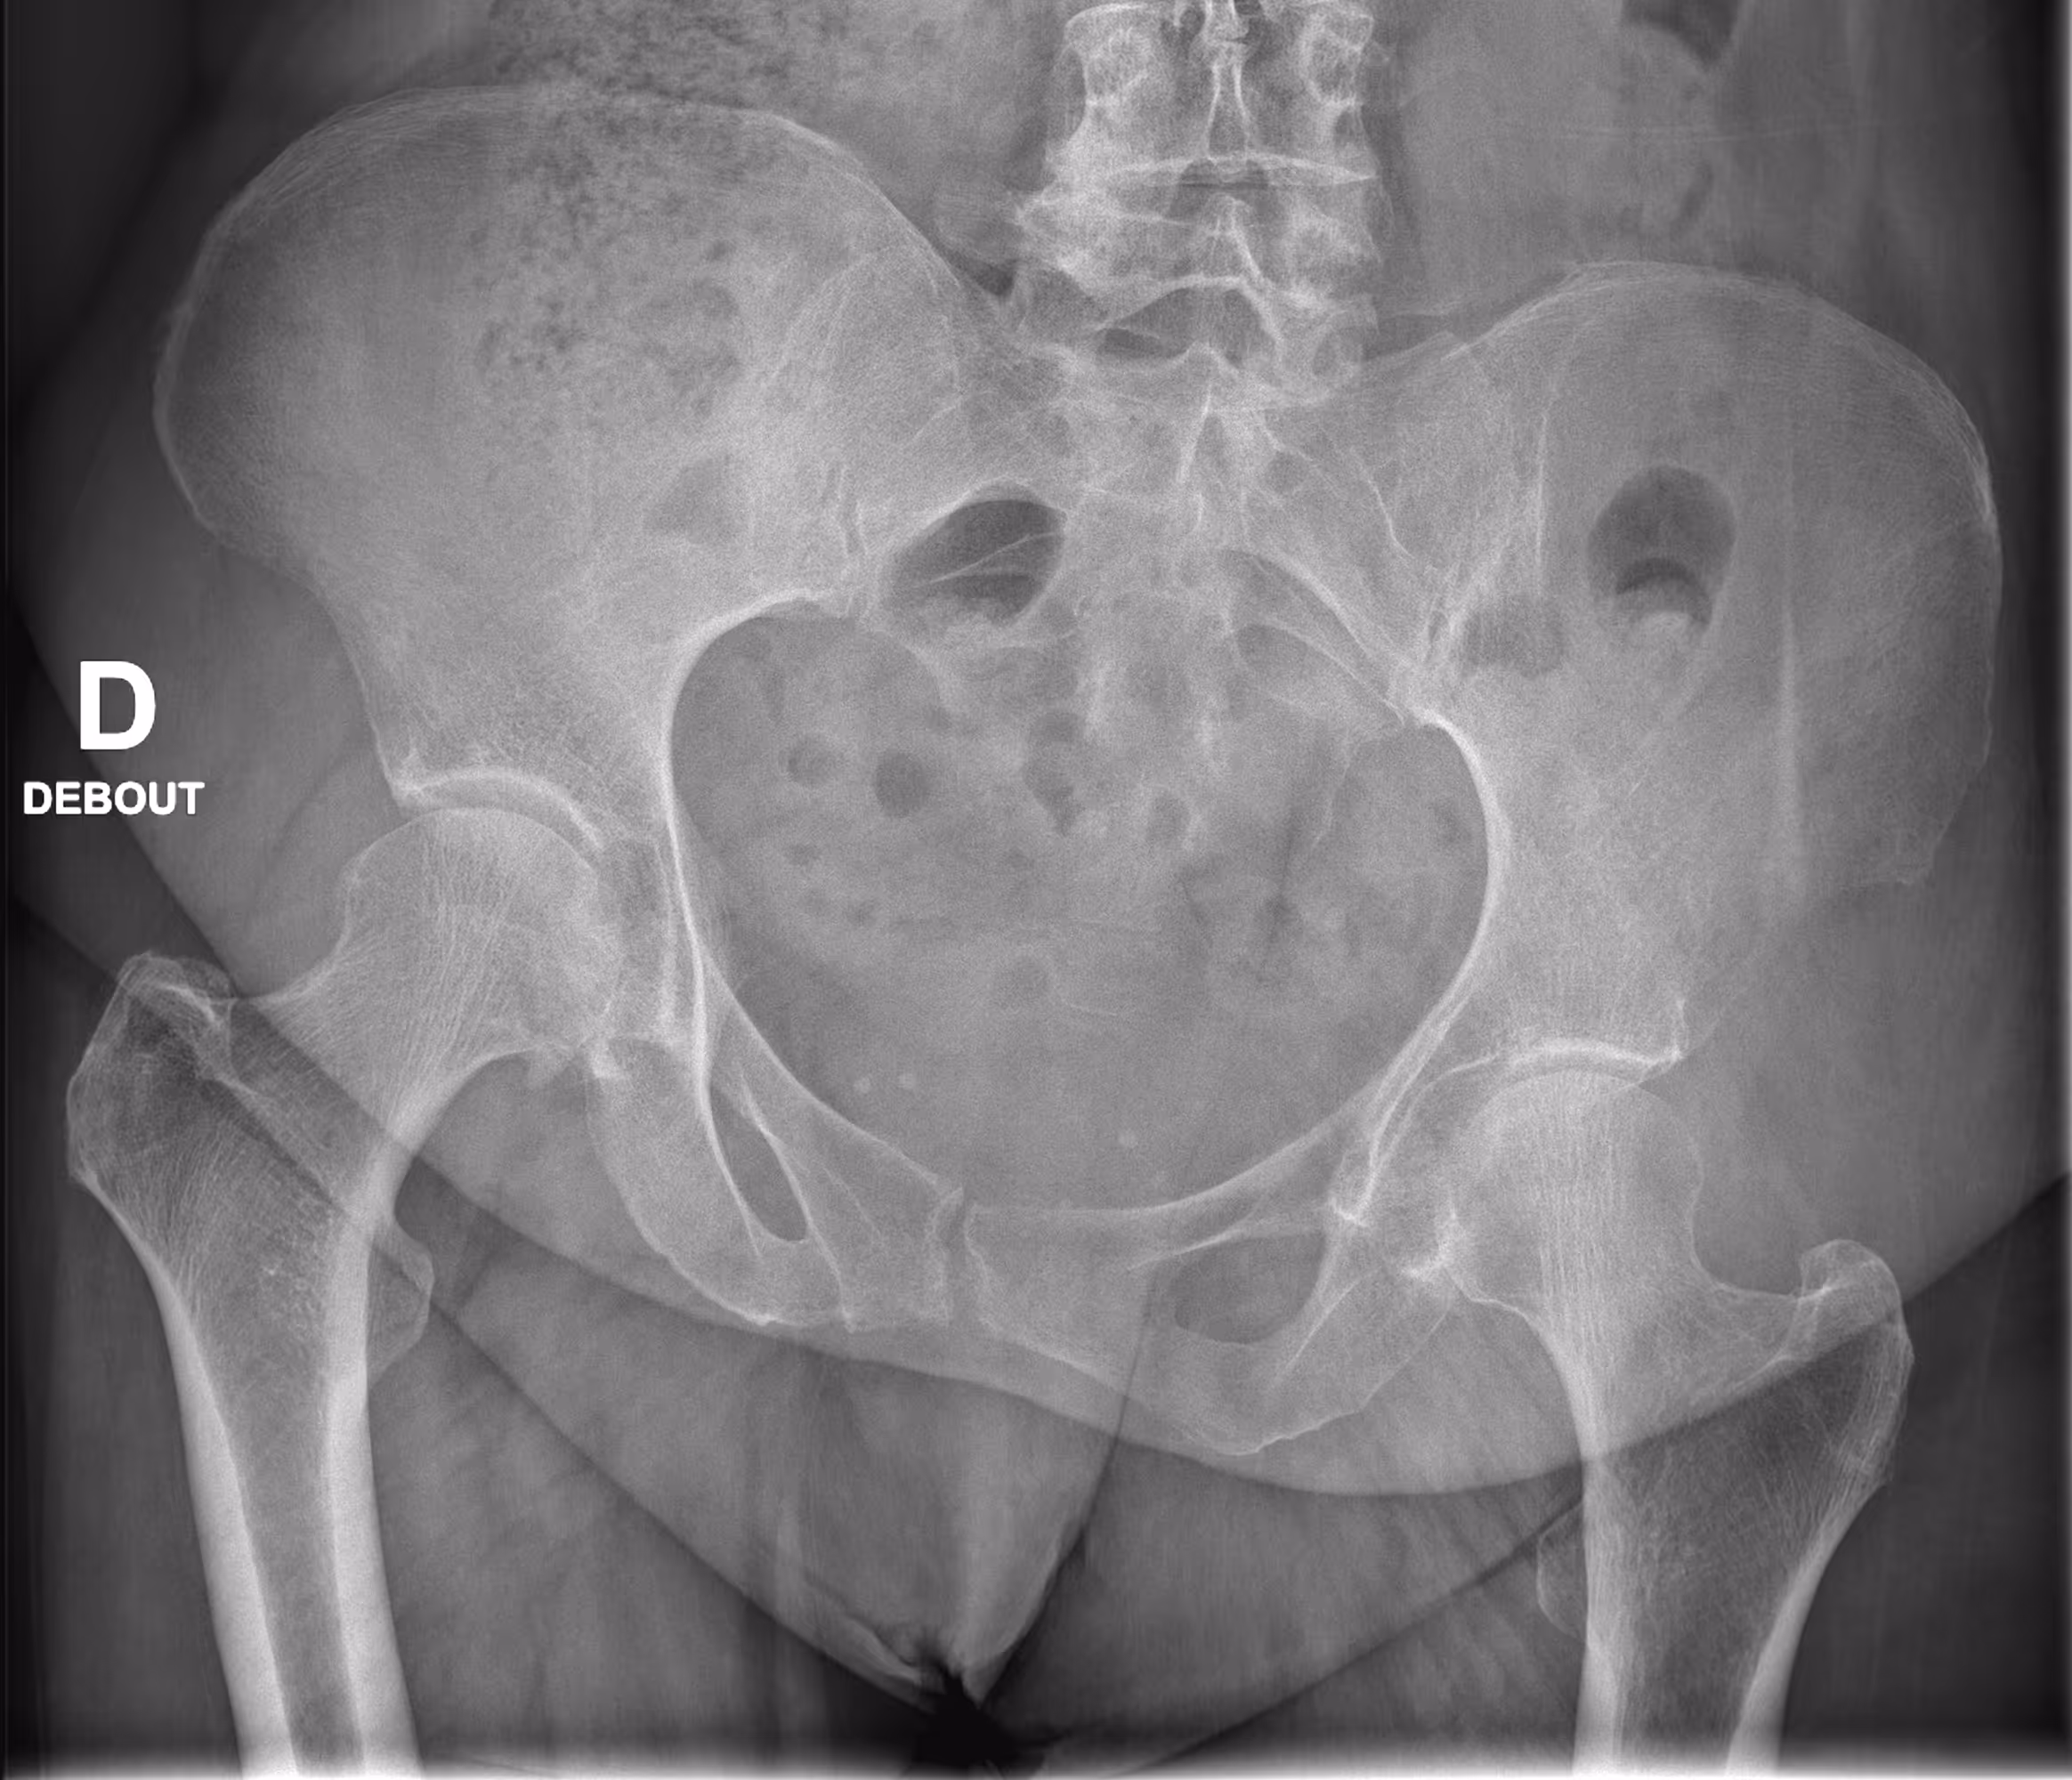

Indication

A 60-year-old female with a history of right hip coxoarthritis presents with left hip pain.

Results

BoneMetrics confirmed the presence of hip dysplasia and inequality of pelvic obliquity.

Frontal

Pelvic obliquity

Acetabular roof angle

Lateral center-edge angle

Caput-Collum-Diaphyseal angle (CCD)

Vertical-center-anterior angle (VCA)

Alpha angle for congenital hip dislocation (on x-ray)